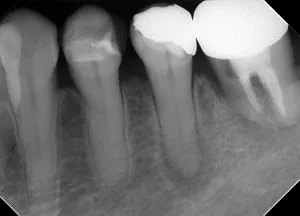

| 術前(写真) | 術後(写真) |

|---|---|

![]() |

| 術名 | 精密根管治療(一回法) |

| 年齢 | 60代 |

| 性別 | 女性 |

| 主訴 | 数ヶ月前から歯ぐきから膿が出ている(他院で歯根破折による抜歯・インプラントを宣告された) |

| 診断名 | 歯内歯周病変(根尖性歯周炎に起因するもの) |

| 治療内容 | ラバーダム防湿下での根管治療、根管充填、支台築造 |

| 治療期間 | 約9ヶ月(治療自体は1日、その後経過観察) |

| 通院回数 | 根管治療自体は1回(その他、経過観察の来院あり) |

| 費用 | 小臼歯 ¥154,000 |

| リスク・副作用 | 歯根破折の程度や歯周病の進行状況によっては、保存が不可能で抜歯が必要になる場合があります。 また、術後に一時的な痛みや違和感が生じることがあります。 |

| 補足事項 | 【診断のポイント】 CT画像にて頬側の骨吸収が確認されましたが、他部位に歯周病がないことや未処置歯(イニシャルトリートメント)であることを踏まえ、 根管治療による骨再生が可能と判断されています。 【経過】 術後1週間でフィステル(瘻孔)が消失し、9ヶ月後にはレントゲン上で骨の完全な再生が確認されました。 |